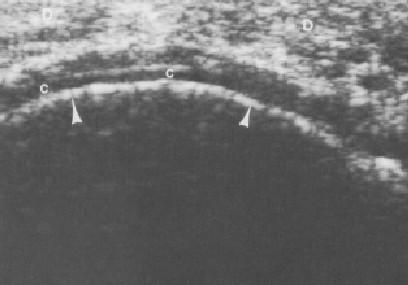

ECOGRAFIA

INDICACIONES DE ECOGRAFIA • Visualización de la Bursa subacromial • Tendones del manguito Rotador • Porción larga del bíceps • Labrum glenoideo

ULTRASONOGRAFIA

• SIGNOS ECOGRAFICOS DE UNA TENDINITIS: • Disminución De La Ecogenicidad Del Tendón • Engrosamiento Del Tendón En Las Formas Agudas Y Adelgazamiento En Los Procesos Crónicos • Focos Hipercoicos O Hipoecoicos En Relación A Zonas De Edemas Y Fibrosis • Calcificaciones Con O Sin Sombra Acústica.